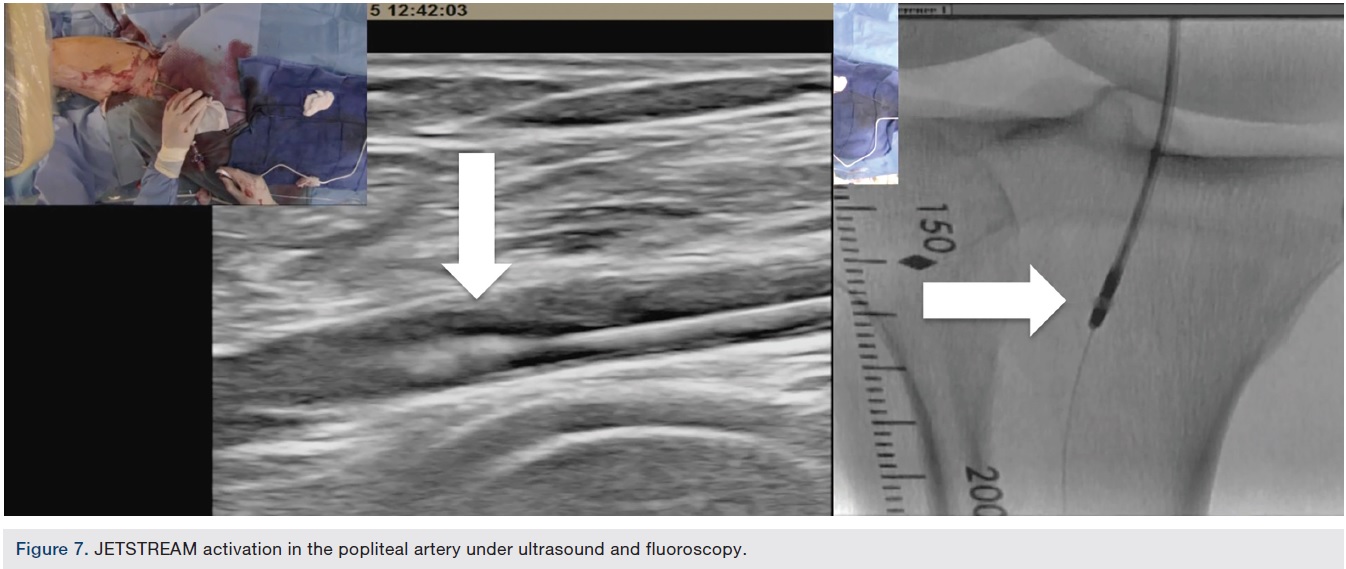

Atherectomy with JETSTREAM. Atherectomy was performed in two stages. During the first stage, we had wire access from the popliteal to the peroneal artery. Before crossing from the posterior tibial, we wanted to treat the popliteal/peroneal segment. A 2.4 mm/3.4 mm JETSTREAM atherectomy device was advanced into the popliteal and activated. The device must be activated with the blades down. A pilot channel will remove some of the plaque. The device is advanced at a rate of no more than 1 mm per second. The operator will need to listen to the pitch of the device. A depressed pitch suggests that the device rotation has slowed down, and the operator should then carefully pull the device back and re-advance. The operator must not allow the aspirational capabilities of the device to be overwhelmed. After successful atherectomy “blades-down,” a “blades-up” run was then performed with the JETSTREAM device (Figure 7). During the second stage of atherectomy, the peroneal and posterior tibial arteries required further therapy. For this stage, we obtained posterior tibial access, crossed the posterior tibial CTO, and snared the posterior tibial wire. We proceeded with the use of a 1.85 mm JETSTREAM device. The tibial device has the rotational capabilities without the “blades-up” feature, and also features active aspiration, like the larger JETSTREAM devices. We were able to atherectomize the posterior tibial and peroneal arteries (Figure 8). Angiographic images post atherectomy demonstrate significant plaque reduction. After atherectomy, we proceeded with kissing balloon angioplasty of the popliteal/peroneal and posterior tibial arteries (Figure 9). Angiography of the popliteal artery post atherectomy showed significant improvement (Figure 10). After removal of the pedal sheath, brisk flow was noted (Figure 11). The procedure was concluded with the resolution of the stenosis from the popliteal artery and restoration of flow in two tibial vessels (Figure 12).